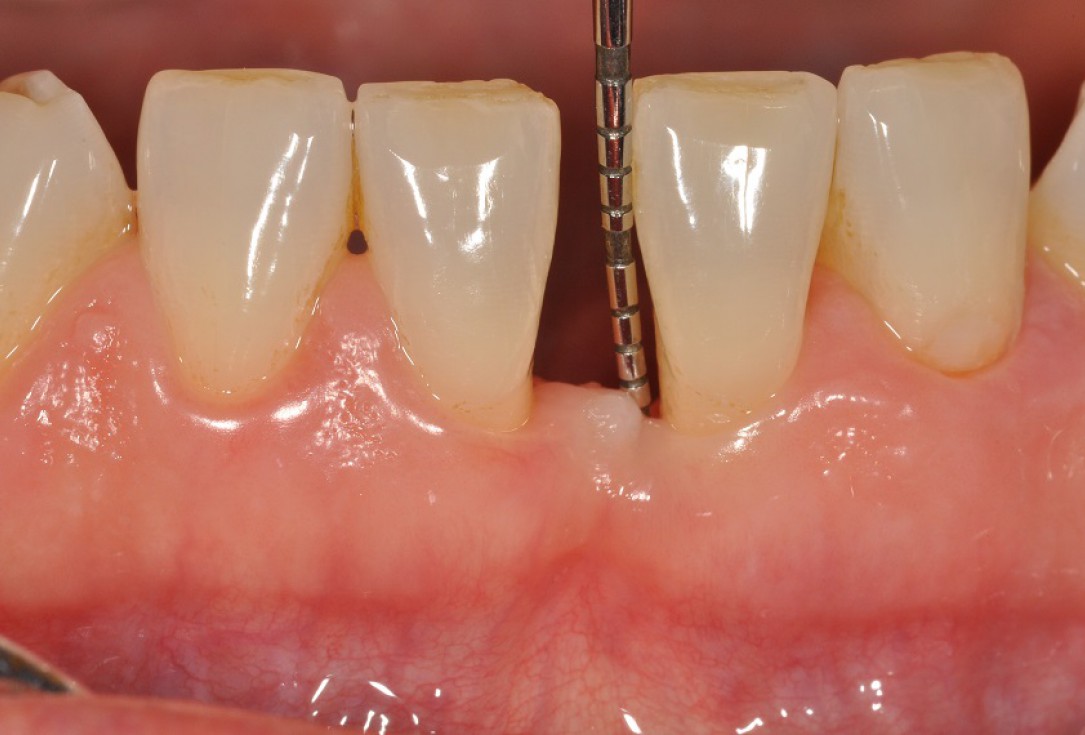

01/13 - Baseline clincial situation and pre-surgical probing.

Wide intrabony defect treated with the modified papilla preservation flap in conjunction with Straumann® Emdogain® and autogenous bone - Dr. B. Molnar